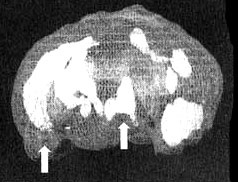

Мозг Пола. Агрессивность

Иллюстрация к книге — Измените свой мозг - изменится и жизнь! [i_080.jpg]

Трехмерное изображение снизу — активный мозг.

Обратите внимание на выраженно повышенную активность в левой височной доле и в поясной системе (стрелки).